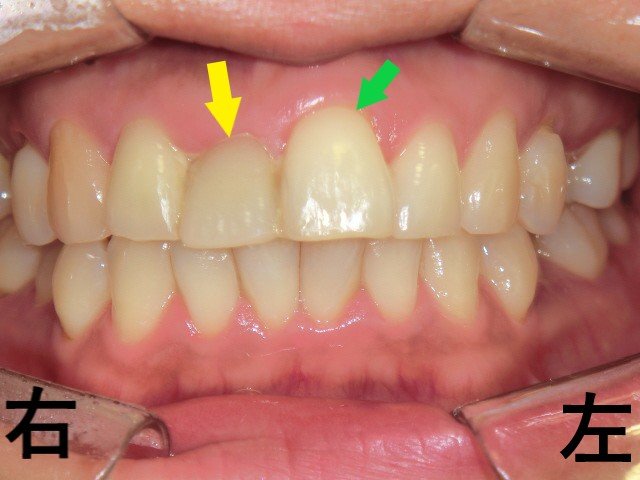

プチ矯正症例40代女性 矯正前

202X年5月、「右上前歯(黄色矢印)の凹みが気になる」という主訴で来院された患者様の症例です。写真をご覧いただくと、右上前歯が左上前歯(緑色矢印)よりも内側に位置して見えるのが確認できます。

しかし、実際には左上前歯が前方に位置しており、それによって右上前歯が凹んで見えている状態でした。